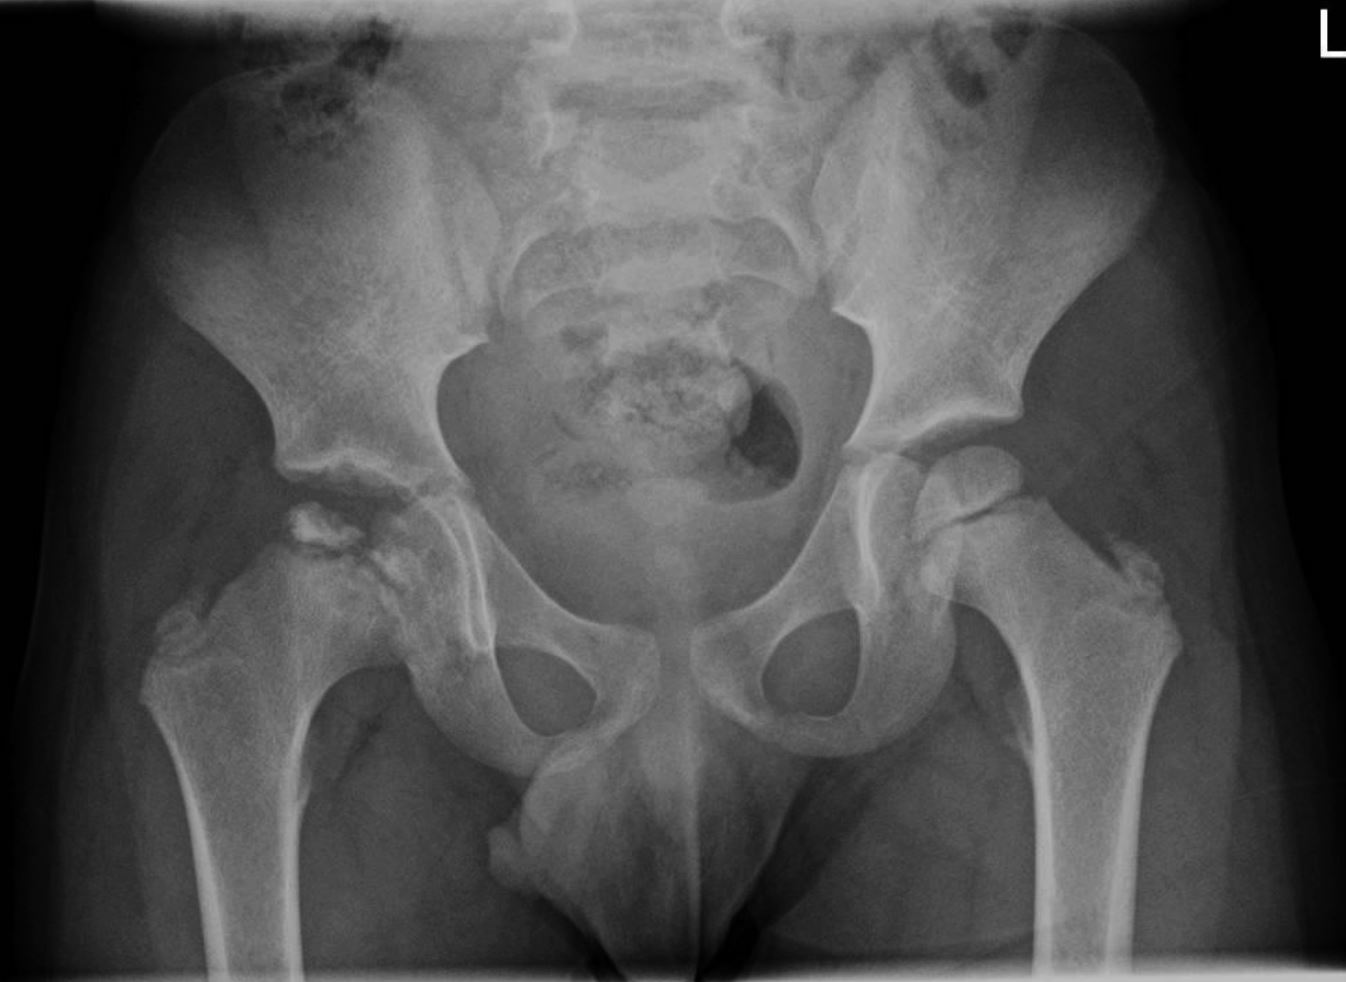

Ein fünfjähriger Junge wird in der Ambulanz der Kinderklinik vorgestellt, weil er bereits seit einigen Monaten sein rechtes Bein beim Gehen ungewöhnlich bewege. Das auffällige Gangbild sei allerdings nicht ständig zu beobachten. Eine Rötung oder Schwellung im Hüftbereich wurde bislang nicht bemerkt. Die Nachfragen zu Infektion oder Trauma werden verneint. Eine Schmerzmedikation sei zu keiner Zeit appliziert worden. Die gestern ambulant durchgeführte Sonografie des rechten Femurs habe allerdings ungewöhnliche Auffälligkeiten ergeben. Daraufhin wird umgehend ein Röntgenbild des Beckens in unserer Klinik angefertigt (Abb. 1).

Abb. 1

: Röntgenbild des Beckens, aufgenommen in einer Ebene anterior-posterior im Liegen

Bildnachweise